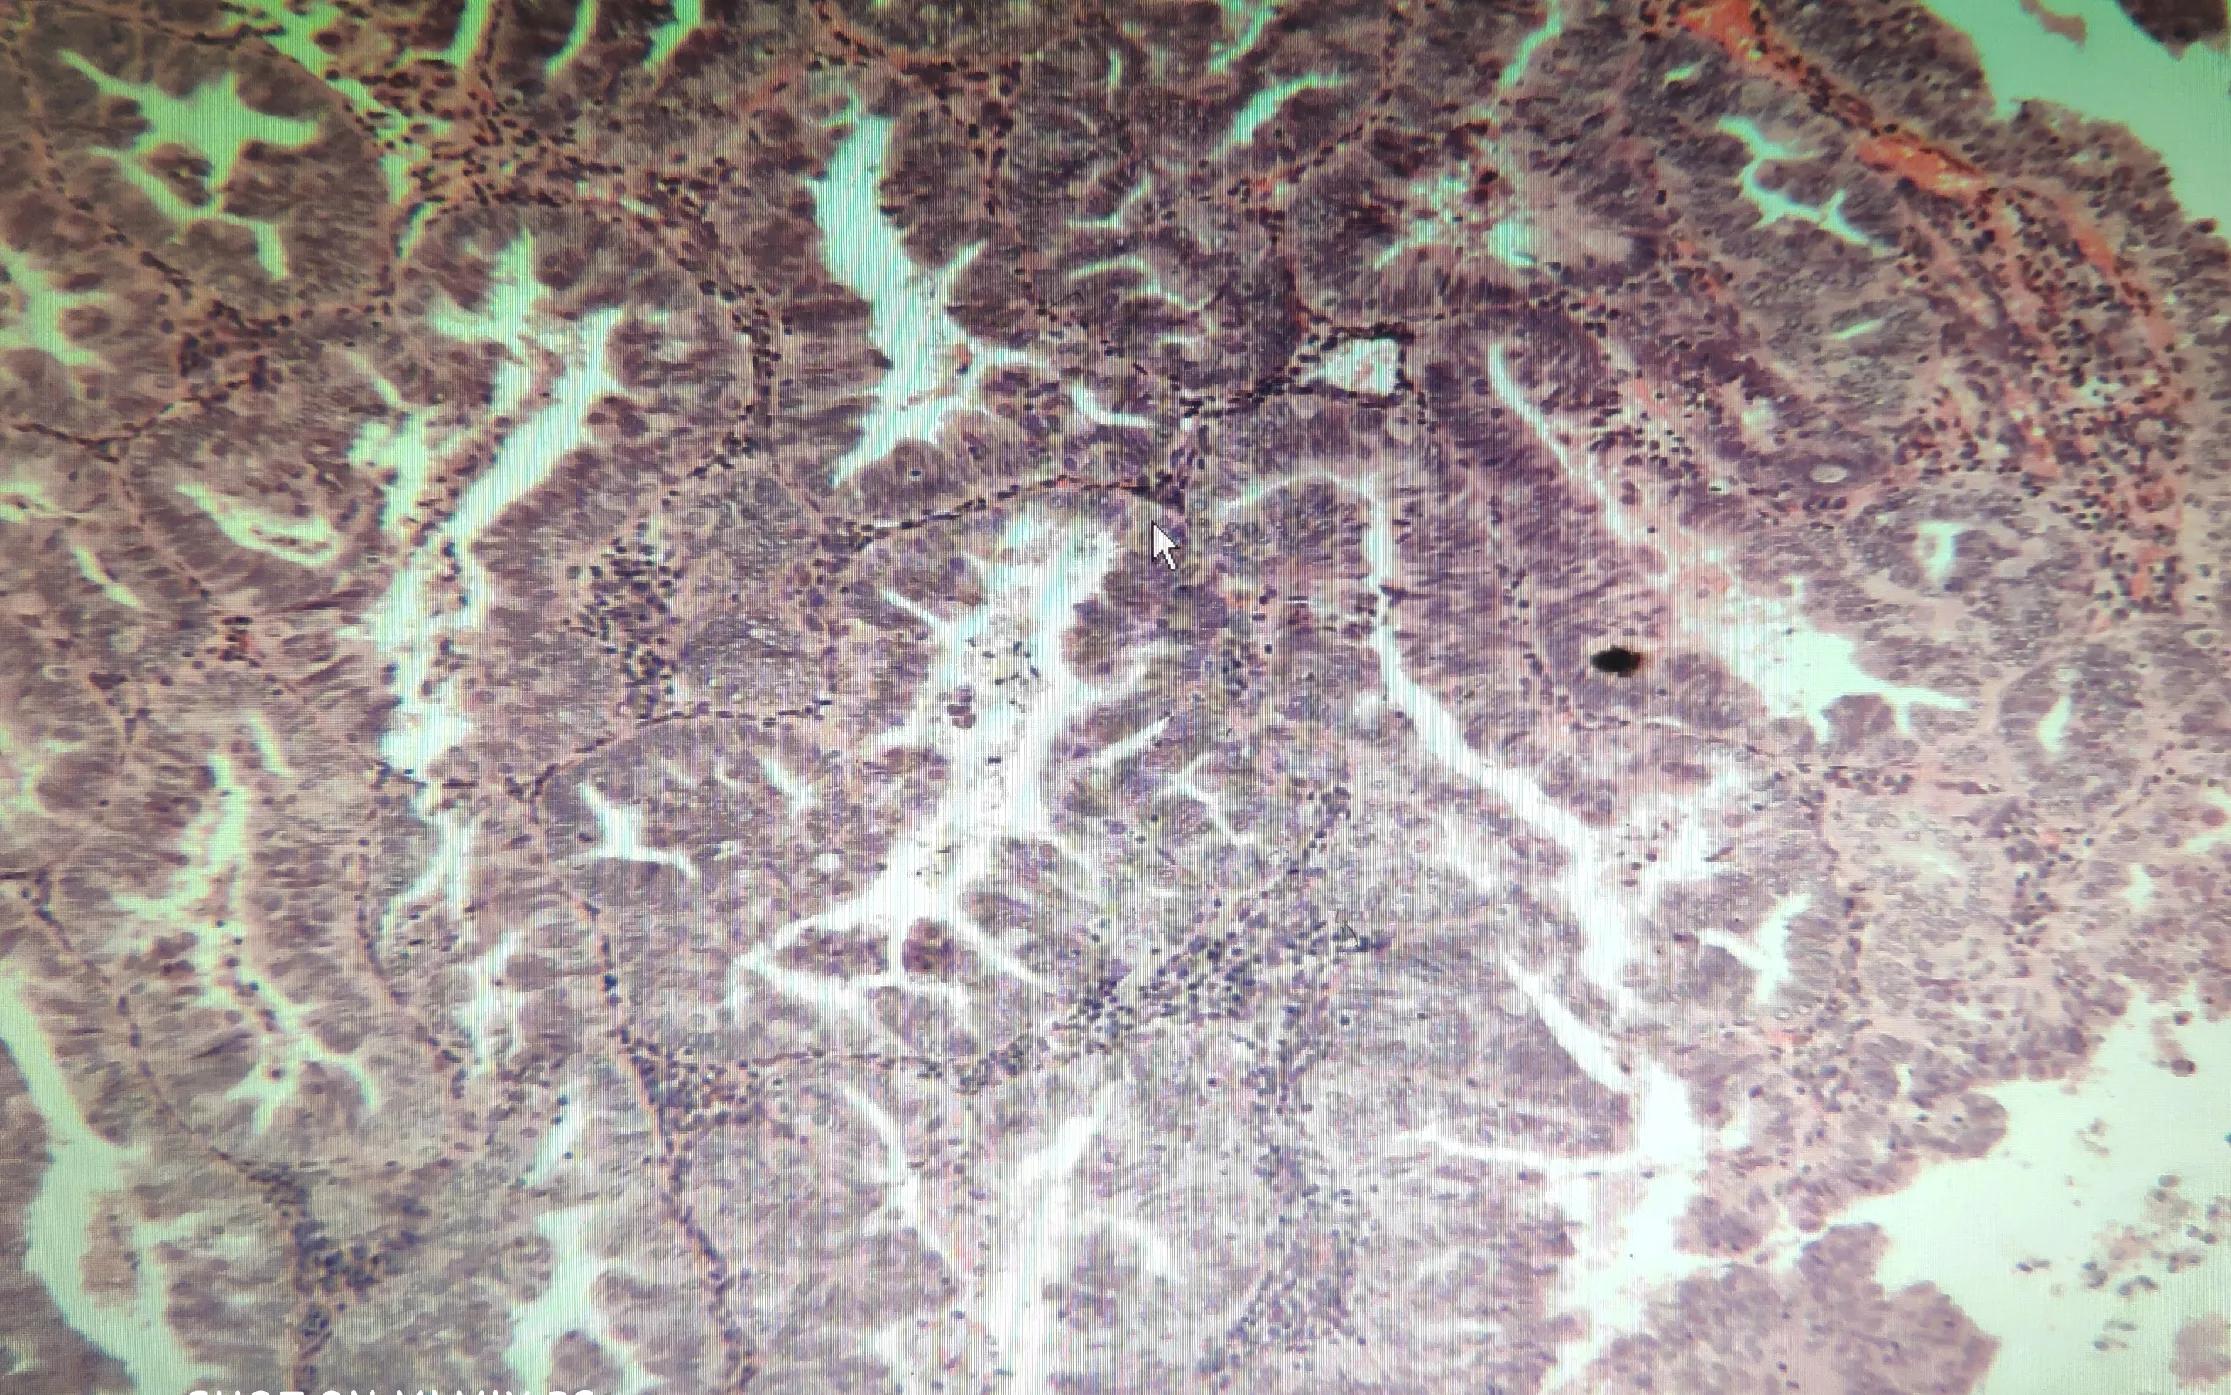

内膜HE切片

术后病理报告:子宫内膜增殖症,伴不典型增生、癌变,(子宫内膜样腺癌)。